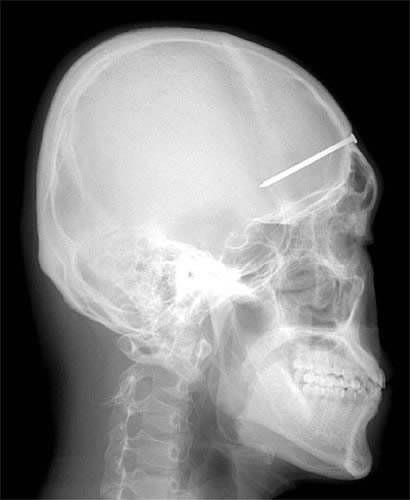

4. Šta kažete na ovaj rendgenski snimak?